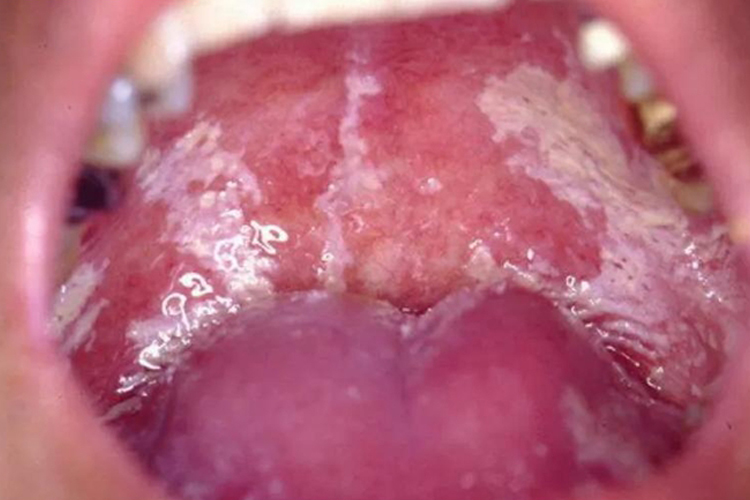

HIV口腔念珠菌感染,口腔黏膜会出现白色假膜或红斑,多伴有疼痛。

HIV口腔念珠菌感染,可出现在口腔黏膜的任何部位,呈乳白色绒状假膜,白色病变周围可见黏膜充血发红,且假膜附着于口腔黏膜表面,不容易擦除,用力擦除后可见出血糜烂面。

此外,还可表现为口腔黏膜上有弥散的红斑,在上腭、颊黏膜有红色斑块,伴有口角糜烂、口干、烧灼感等症状。